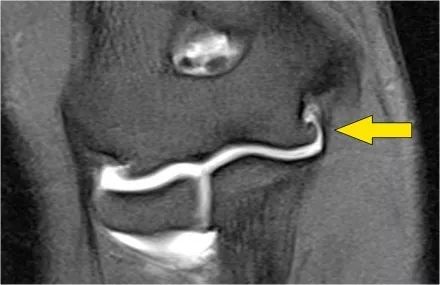

通过将隧道放置在内侧上髁中来完成UCL修复。它们对耸高的结节进行了操作,并在它们之间放置了移植物。

这张射线照片是一名26岁的职业棒球运动员,他曾进行过UCL重建。注意隧道(箭头)。这种操作通常很有效。

MR图像,您可以看到内侧上髁的隧道。

在尽管高低不平的冠状图像几乎看起来像一个正常的UCL。